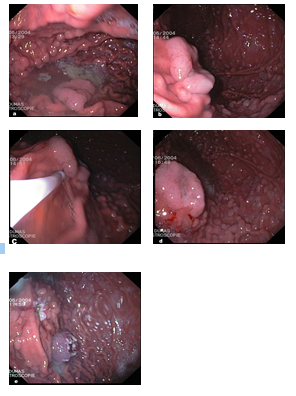

A 24-year-old man, smoker, previously diagnosed with FAP. His father has also been diagnosed as having FAP. He underwent a prophylactic total colectomy with ileoanal anastomosis, when he was 16 years old. He presented to our institution for endoscopic follow-up and surveillance planning. A rectoscopy was performed and showed normal pouch. At the same time, upper gastrointestinal endoscopy was done and showed a tiny 3 mm duodenal polyp, removed by snare polypectomy. The antrum mucosa was normal, but the body and fundus were carpeted with small polyps ranging in size from 2 to 5 mm. In addition, there was a large 2.5cm “ear shape” polyp, located in the midfundus,along the greater curvature (Figure 2a and 2b).

2a- Endoscopic view showing FGPs, with one large sessile polyp in the midfundus. 2b- Large polyp in the fundus with background of fundic gland polyps. 2c & 2d- Saline sub mucosal injection of the large polyp to be ready for mucosectomy. 2e- Large polyp (2.5 cm) was safely removed by polypectomy snare

Figure 2:

2a- Endoscopic view showing FGPs, with one large sessile polyp in the midfundus.

2b- Large polyp in the fundus with background of fundic gland polyps.

2c & 2d- Saline sub mucosal injection of the large polyp to be ready for mucosectomy.

2e- Large polyp (2.5 cm) was safely removed by polypectomy snare

Subsequent endoscopic ultrasound of the fundus proved no extension beyond the mucosa. Multiple biopsy specimens were obtained from small polyps as well as large polyp. Pathological examination of small fundic polyps showed simple hyperplasia of the fundic glands and microcysts consistent with FGPs. Biopsies from the large polyp proved tubular adenoma. Later on, the patient underwent another therapeutic endoscopic session for endoscopic mucosal resection of the large fundic polyp after saline sub mucosal injection (Figure 2c, 2d, 2e). Histopathologically, the large fundic polyp measures 22 x10 x18 mm, displayed moderate focal glandular epithelial atypia, nuclear enlargement, and pseudo-stratification, with some regular mitoses consistent with dysplastic tubular adenoma, intimately related to FGP without evidence of malignancy (Figure 3a and 3b).